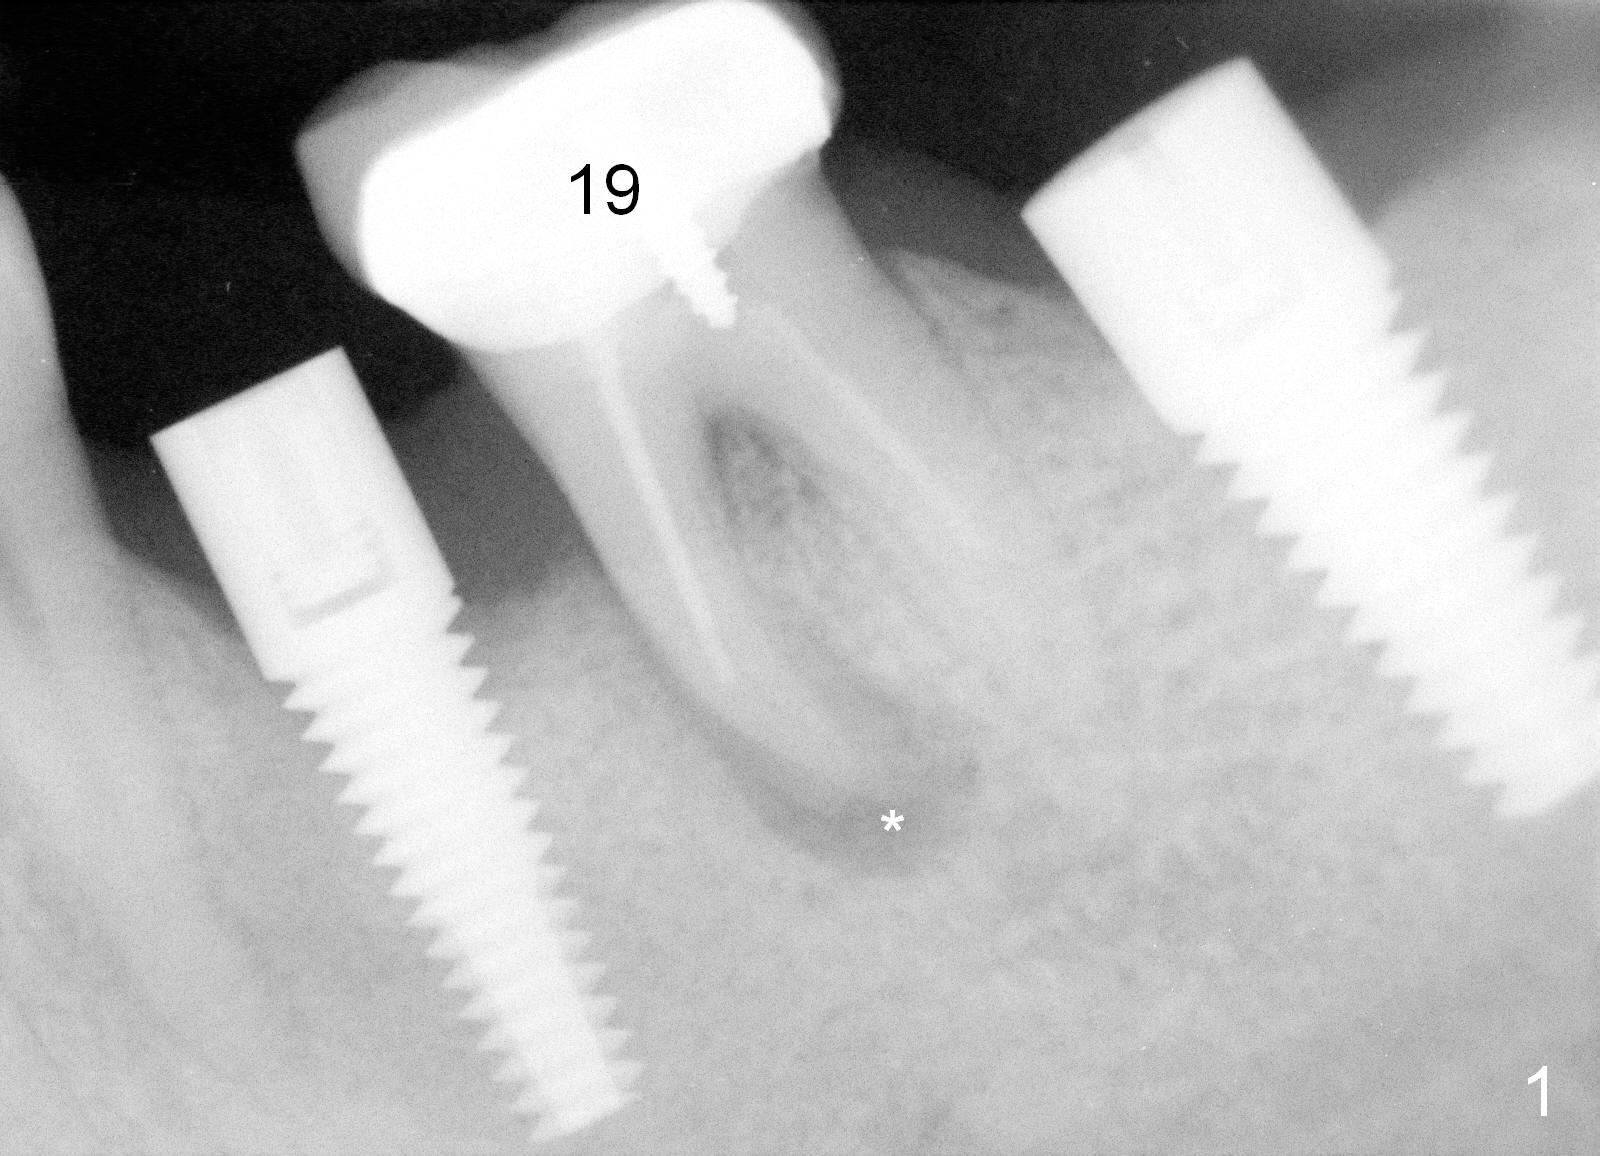

When the infection at the site of #20 is under control, the tooth #19 causes severe pain with mesial periapical radiolucency (Fig.1 *). Vertical mesial root fracture is confirmed at extraction. Osteotomy is initiated in the septum (Fig.2 S), but the apical end of the 2 mm pilot drill deviates to the mesial socket. A Lindamann bur is used to move osteotomy distal, but the implant (6x17 mm) is mainly placed in the mesial socket (Fig.3). An intraop drawback associated with the deviation is pain control. The nervous patient questions several times whether it is a good idea to place an implant in the infected site. Block anesthesia has to be administered. In fact lack of pain control may be also related to proximity to the Mental Loop (Fig.3 red dashed line). Fortunately no paresthesia occurs postop, since the implant is somehow placed lingually.